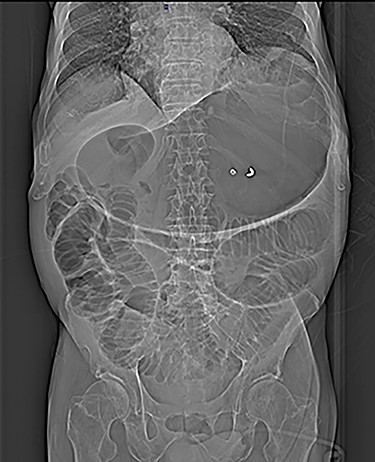

Plain abdomen radiography was performed at the ED and showed distended stomach and small bowel with air-fluid levels (Fig. 1). No free gas in the peritoneal cavity was seen. A contrast-enhanced CT scan revealed a huge gastrectasia with liquids, small bowel distention due to a suspected adherent bridle. Some loops of the ileum showed emphysematous walls (Fig. 2). A minimal perihepatic liquid effusion was observed due to suffering bowel.

Plain abdomen radiography shows distended stomach and dilatated loops of bowel without free gas in the peritoneal cavity.